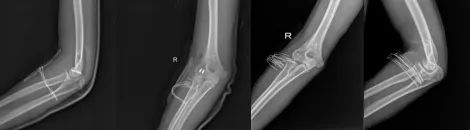

术后影像